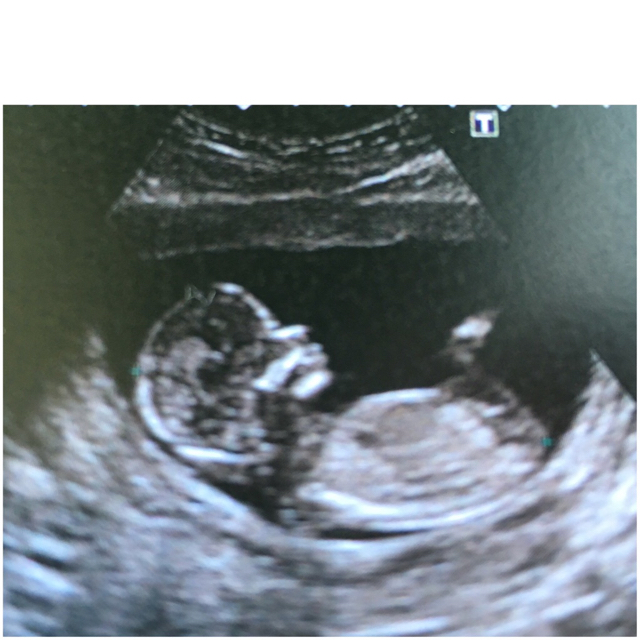

Ooh ladies can I but in too lol. I don't see any penis looking bits on either of your nub shots. Can you guess mine too? PleaseAttachment 31845

Manz83 yours looks girly. The other two scans posted, I can't see any clear nub shots sorry!